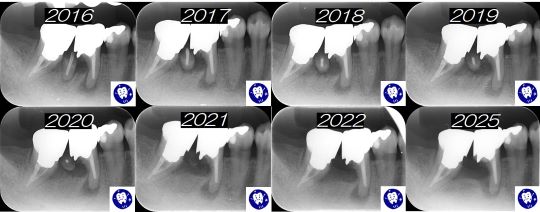

細かくてあまりよく見えないかもしれませんが(あえてそうしていますが)、2016年に初めて来院されたときにはすでに右下の奥から2番目の歯の根がむし歯で折れています。

通常であれば抜歯→前後の歯の詰め物や被せ物を削って外してブリッジ、というところですが、患者さんが残してほしい(というよりは抜くのが怖いの方が強かったかも?)というご希望だったので、他の悪い歯を治療を優先しながら様子を見ていくことにしました。

実際のところは一番奥の歯の根も虫歯になっているのでブリッジもできず、2本抜歯すると入れ歯になってしまう(もちろんインプラントは怖くてできない・・・)ためにやむを得ず残した、という側面もあったかと思います。

ところが、他の悪い歯の治療が終わってもどうしても抜く決心がつかないため、そのままメンテナンス(定期検診)に移行することになりました。

ここで、この患者さんの凄いところは、ほぼ10年間真面目に3か月ごとに通われてメンテナンスを継続されたことで、その結果、折れた根は溶けてなくなりながら排出されて、その後も悪い部分の骨は多少は溶けながらも(最低限でとどまっているとも言えると思います)それ以外の部分の骨は全く溶けずに、またその他の部分の虫歯が進行することもなく、お口全体を見ても歯が悪くなる進行が食い止められていることがわかりました!

もちろん通われている中で歯磨きの仕方や食習慣の注意点などを身につけられてきっちりと自己管理されるようになったことが大きい訳ですが、メンテナンスの意味合いとしてとてもわかりやすい結果だなぁ・・・、と思ってとてもうれしく感じた次第です。